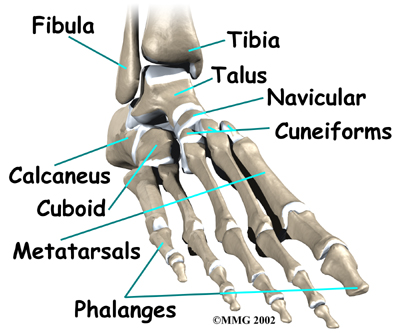

The big toe in medical terms is called the hallux. The joint at the base of the big toe is called the metatarsophalangeal, or MTP, joint. Like any other joint in the body, the joint is covered with articular cartilage, which is a slick, shiny covering on the end of the bone. If this cartilage is injured, it begins a slow process of wearing out, or degeneration. The articular surface can wear away so much that eventually raw bone rubs against raw bone.

Bone spurs form around the joint as part of the degenerative process. The spurs, or bony outgrowths, may restrict the motion in the joint, especially the ability for the toe to bend upward as the body moves forward over the foot, such as when you are taking steps. The big toe becomes very stiff or immobile into this range of motion, hence the reference to rigidity in the name of this condition.